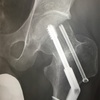

5週間後の2017年12月に病院に行きました。部屋に入るなり、先生はマウスをカチカチして興奮しながら早口で言いました。

「これ見てください!完全にくっついてる。これはついたと思います。折れたところが埋まったでしょ。これは勝ったな、これは勝ったぞ」

こんなに興奮した様子の先生は初めて見ました。体重をかけた事で骨に刺激が加わり、骨癒合が促進されたようです。やはり骨には体重をかけないと治る力が戻ってきません。だから体重をかけたくて仕方がなかった。しかし、あまり早期に体重をかけてしまうとズレてしまう。4ヶ月もの免荷に耐えられなくなり、セカンドオピニオンをもらおうか、勝手に荷重開始しやうかと悩んだこともありました。

元々、O先生の上司は人工股関節という判断でした。そこを彼は上司に逆らって骨接合という選択を患者に勧めて、その結果がやはりダメだとしたら、批判は免れ得なかったでしょう。彼にとってもリスクを取った手術だったのです。それで興奮していたのかもしれません。